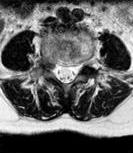

• 单侧双通道内镜与经皮椎间孔镜技术治疗极外侧型腰椎间盘突出症的临床疗效对比

2025, 31(6):9-16. DOI: 10.12235/E20240622

摘要 (318) HTML (258) PDF 1.17 M (159) 评论 (0) 收藏

摘要:目的 比较单侧双通道内镜(UBE)与经皮椎间孔镜下髓核摘除术(PTED)治疗极外侧型腰椎间盘突出症(FLLDH)的临床疗效。方法 回顾性分析2021年3月-2023年3月于该院进行治疗的FLLDH患者42例,根据手术方法不同,将患者分为UBE组(18例)和PTED组(24例)。记录并比较两组患者手术时间、术中透视次数、住院时间和围手术期并发症等指标。采用疼痛视觉模拟法(VAS)评估疼痛程度,Oswestry功能障碍指数(ODI)评估功能障碍情况,Macnab评分标准评估临床疗效。结果 UBE组手术时间为(95.56±20.94)min,较PTED组的(78.25±17.23)min长,术中出血量为(69.17±8.95)mL,较PTED组的(23.96±5.89)mL多,差异均有统计学意义(P < 0.05)。UBE组住院时间为(5.67±1.28)d,与PTED组的(5.33±1.05)d比较,差异无统计学意义(P > 0.05)。UBE组术中透视次数为(3.00±0.77)次,明显少于PTED组的(7.42±0.93)次,差异有统计学意义(P < 0.05)。两组患者术后VAS评分和ODI较术前明显降低,差异均有统计学意义(P < 0.05)。术后3 d,UBE组腿痛VAS评分为(3.28±0.58)分及ODI为(41.17±4.30)%,明显低于PTED组的(4.13±0.74)分及(45.50±3.91)%,差异均有统计学意义(P < 0.05),但两组患者术后3个月和1年的VAS评分及ODI比较,差异均无统计学意义(P > 0.05)。两组患者优良率比较,差异无统计学意义(88.9%和87.5%,P = 0.563)。PTED组围手术期出现神经损伤2例,UBE组无神经损伤出现,两组均无感染、复发和大出血等严重并发症发生。结论 PTED与UBE两种手术方式治疗FLLDH均安全和有效。但UBE术中透视次数少,镜下视野更加清晰,神经损伤风险更小。